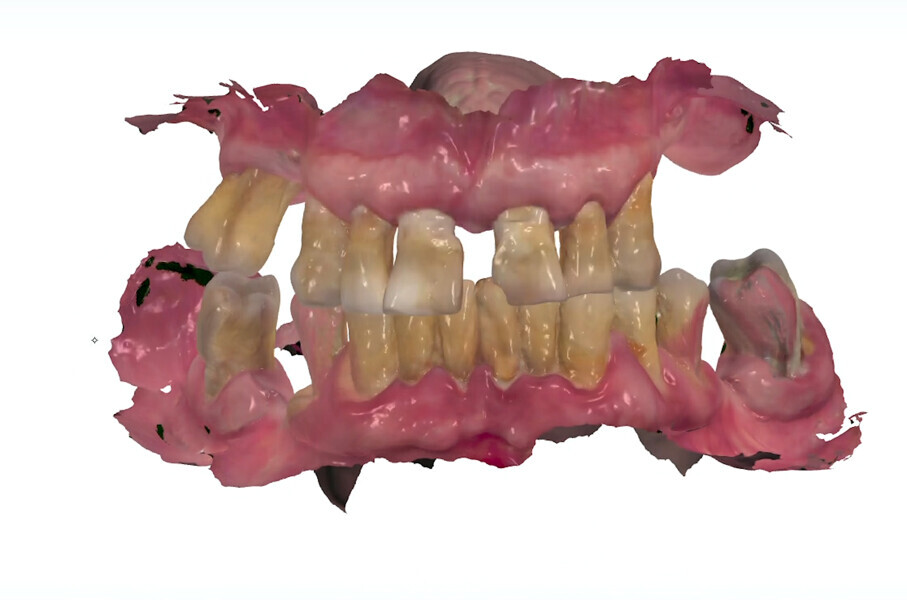

The fully digital Pro Arch protocol